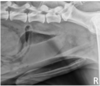

What is shown in this image?

A

prostatomegaly

-occupies ~ 90% of pelvic inlet diameter

-irregular, ill-defined margins